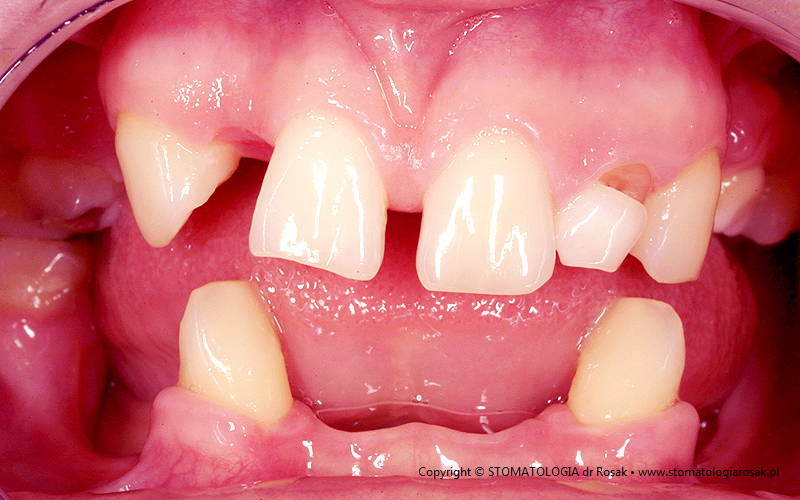

5. Pacjentka lat 18 z wrodzonym brakiem wielu zębów tzw. hipodoncją – rehabilitacja protetyczna z wykorzystaniem

stałych mostów porcelanowych na podbudowie metalowej.

| 5a. Stan przed leczeniem |